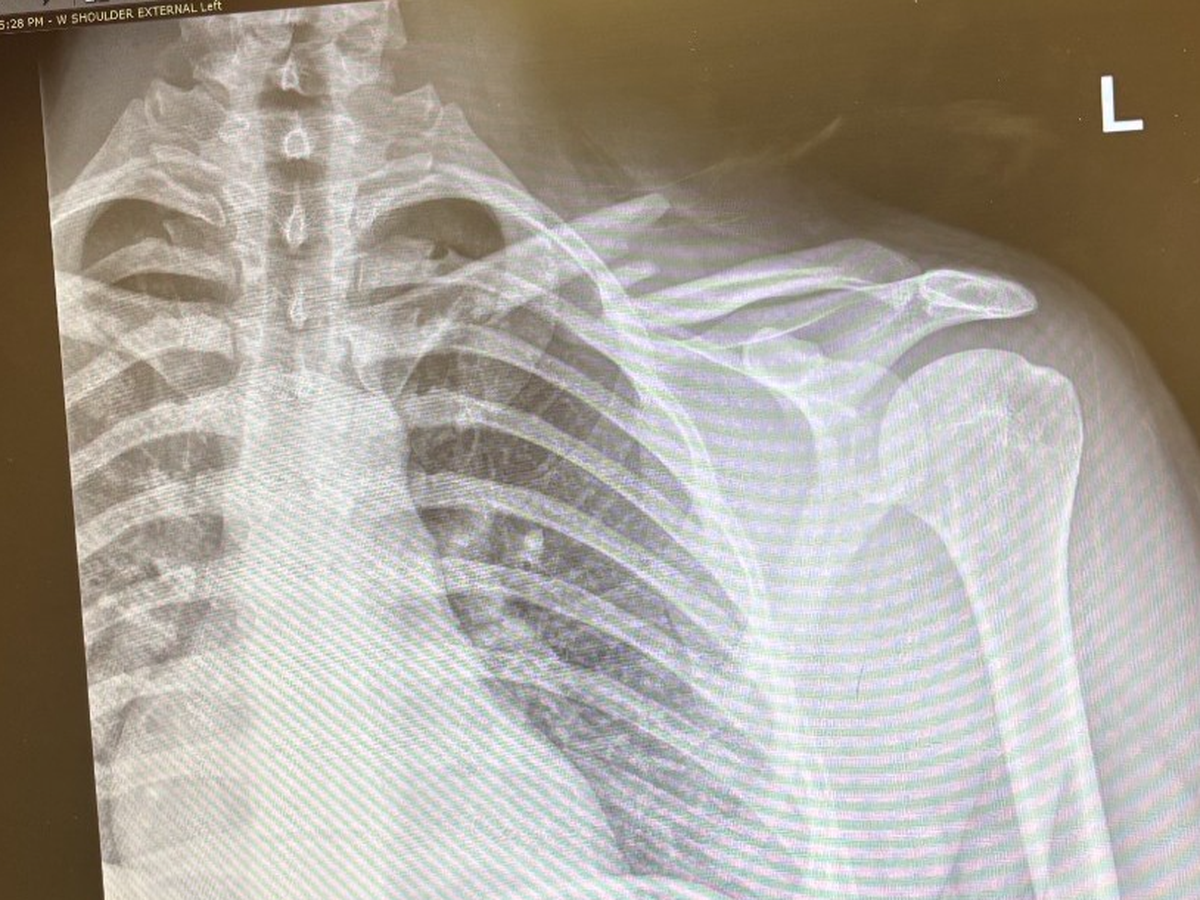

Hello, my name is val and I'm creating a gofund me for my younger brother Simon, who had an accident, unfortunately while training he broke his collarbone in two places and required surgery with plate and screws, along with a physical therapy. He won't be able to work for 10 weeks and the medical bills will be coming soon, that he won't be able to pay, our family is trying our best to help but it isn't enough, if you can help to contribute I would greatly appreciated it.